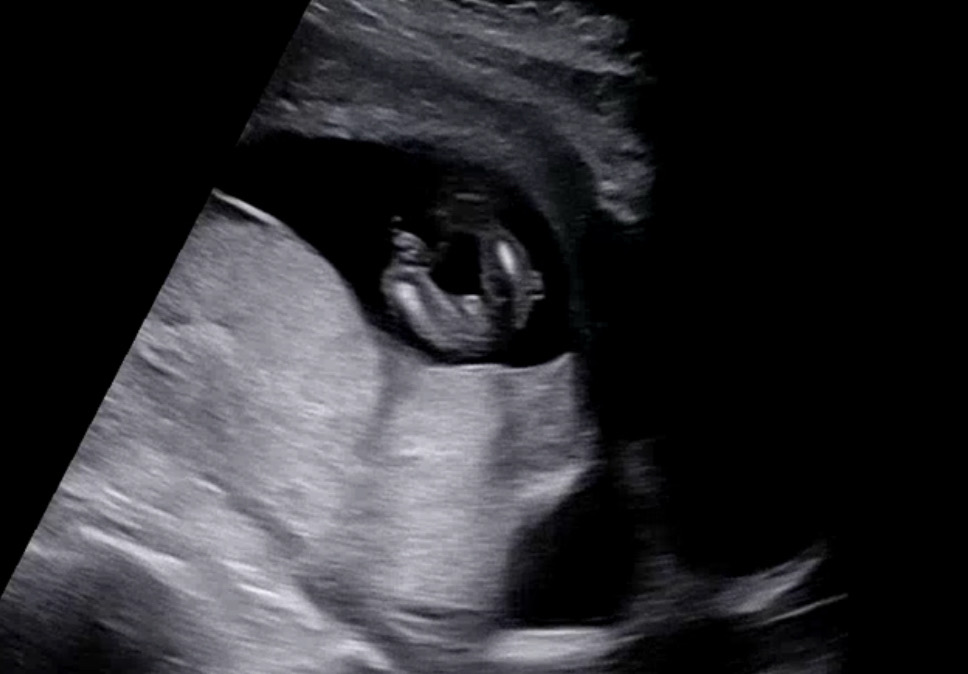

14주 다리사이 딸일까요 아들일까요

예정일 상 14주 2일 초음파 상 아기 크기에 따른 주수는 14주 4일이에요! 다리사이에 뭔가가 보이는 것도 같은데 딸일까요 아들일까요🫣 몇시간째 들여다보고 있는 중..🤦🏻♀️

어머 혹시 얼마나 확연히 드러나있었던 걸까요..? 저정도도 확연한건지.. 아직 일주일이나 남아서 매일 들락날락 거리는 중이네요.....ㅋㅋㅋㅋ